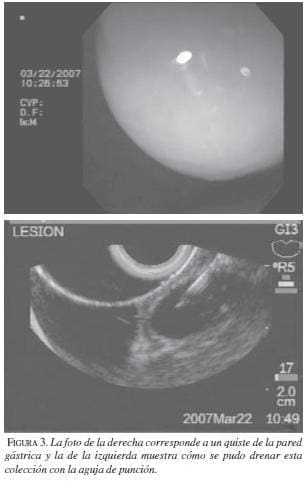

Los primeros en describir la técnica fueron Wierseman y colaboradores (11). La localización de los ganglios celiacos en la raíz del tronco celiaco es fácil por ecoendoscopia debido a la proximidad de éste con la pared gástrica (figura 1). Una vez se ubica el tronco celiaco, se puede utilizar una técnica central en la cual se aplican 20 ml de alcohol al 98% (figura 2) o una técnica bilateral en la cual se aplican 10 ml a lado y lado del tronco celiaco. Las dos técnicas tienen una eficacia similar; nosotros preferimos la primera debido a su facilidad. Antes del alcohol, siempre se deben aplicar 10 ml de mebucaína al 0,5%. Lo que se busca es una neurólisis química del plexo celiaco.

La imagen de las colecciones o los abscesos puede diferenciarse claramente de las estructuras normales y existen diferentes accesorios que permiten acceder a ellos y drenarlos, complementando el procedimiento con antibióticos, lo cual evita en muchos casos una intervención quirúrgica que, hasta el momento, era la conducta tradicional. En la literatura hay varios reportes exitosos de esta aproximación, como el del grupo de Virginia (14), que logró un drenaje exitoso de un absceso mediastinal, y el de Seedwald y colaboradores (15), quienes drenaron exitosamente un absceso subfrénico en dos pacientes figura 3.